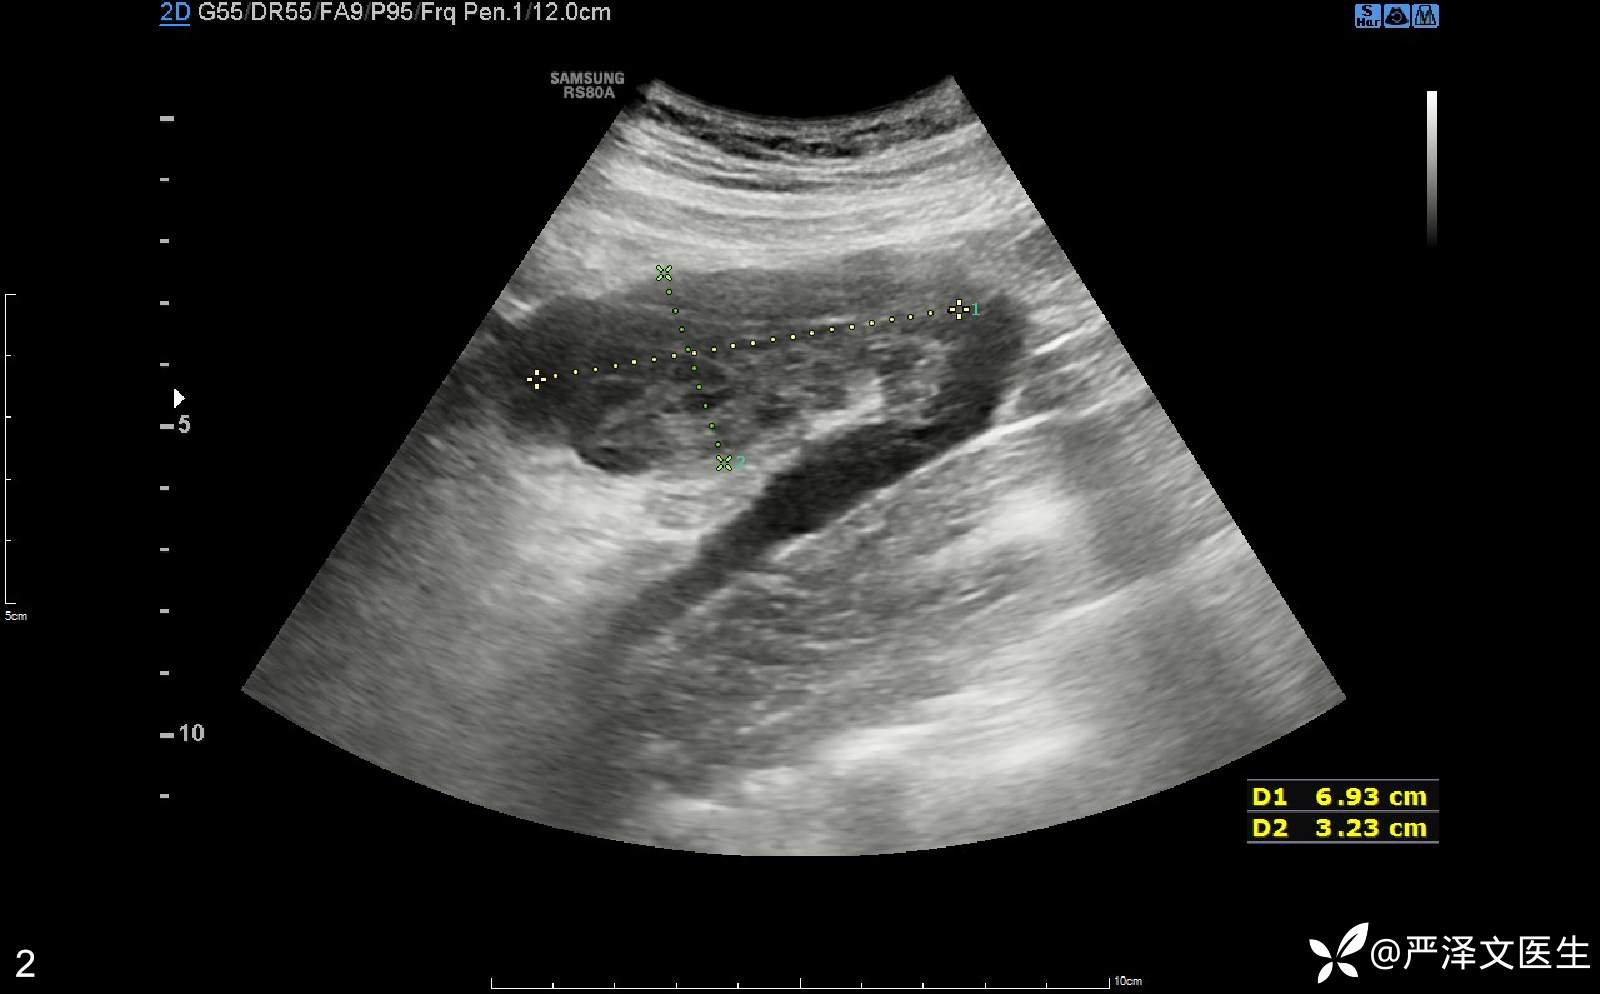

腹部彩超(04-01):(右侧中腹)见混合回声区,大小约69×32mm,边界清,其与血管相连,CDFI:内见血流信号,呈静脉频谱。检查意见:临床所指处(右侧中腹)见一混合回声区,请结合临床。(见图2、3、4、5)

混合回声、增大的阑尾